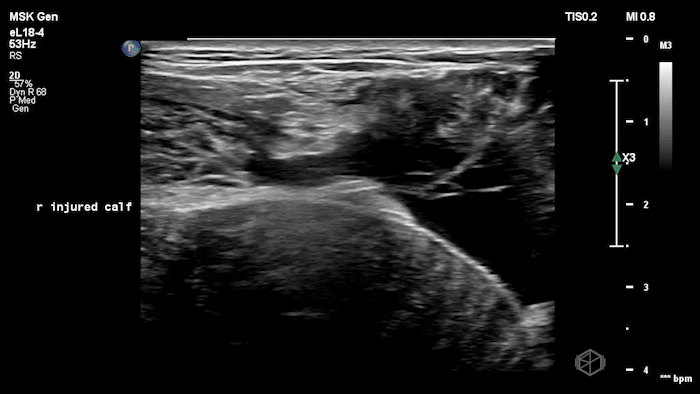

20 - What is the diagnosis?

Gastrocnemius tear